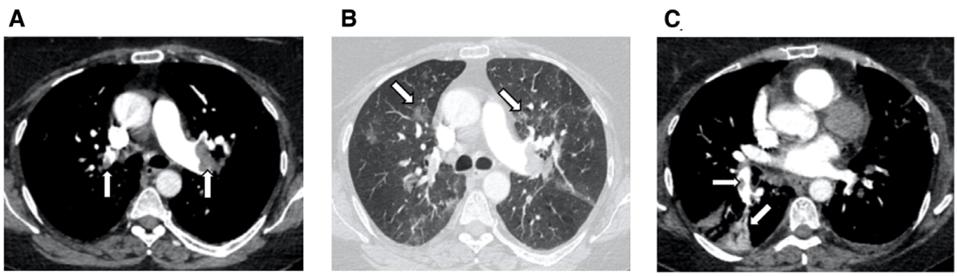

案例1: 这是2020年疫情早期Thorax杂志发表的一篇重要文章,患者COVID-19疑诊后,核酸检测阴性,但入院前一天D-二聚体2560 ng/mL(正常<500 ng/mL),临床医生敏感性非常高,进行了VTE预防。

入院后,患者就出现了呼吸困难,第3天病毒RT-PCR拭子阳性,行CTPA提示肺栓塞。

图:双侧主肺和肺叶动脉PE,右下叶楔形梗死

图:肺动脉段水平PE

肺部CT影像没有很多病毒性肺炎的改变,但在双下肺能看到一些类似磨玻璃样或实变的阴影,这种阴影在很大程度上可能和血栓密切关联。

这位接受肝素治疗5天后改用口服抗凝药物,好转出院了。这是早期非常重要的病例,其中强调D-二聚体的诊断价值,但 是不是D-二聚体阴性就能完全除外肺栓塞呢?其实并非如此。